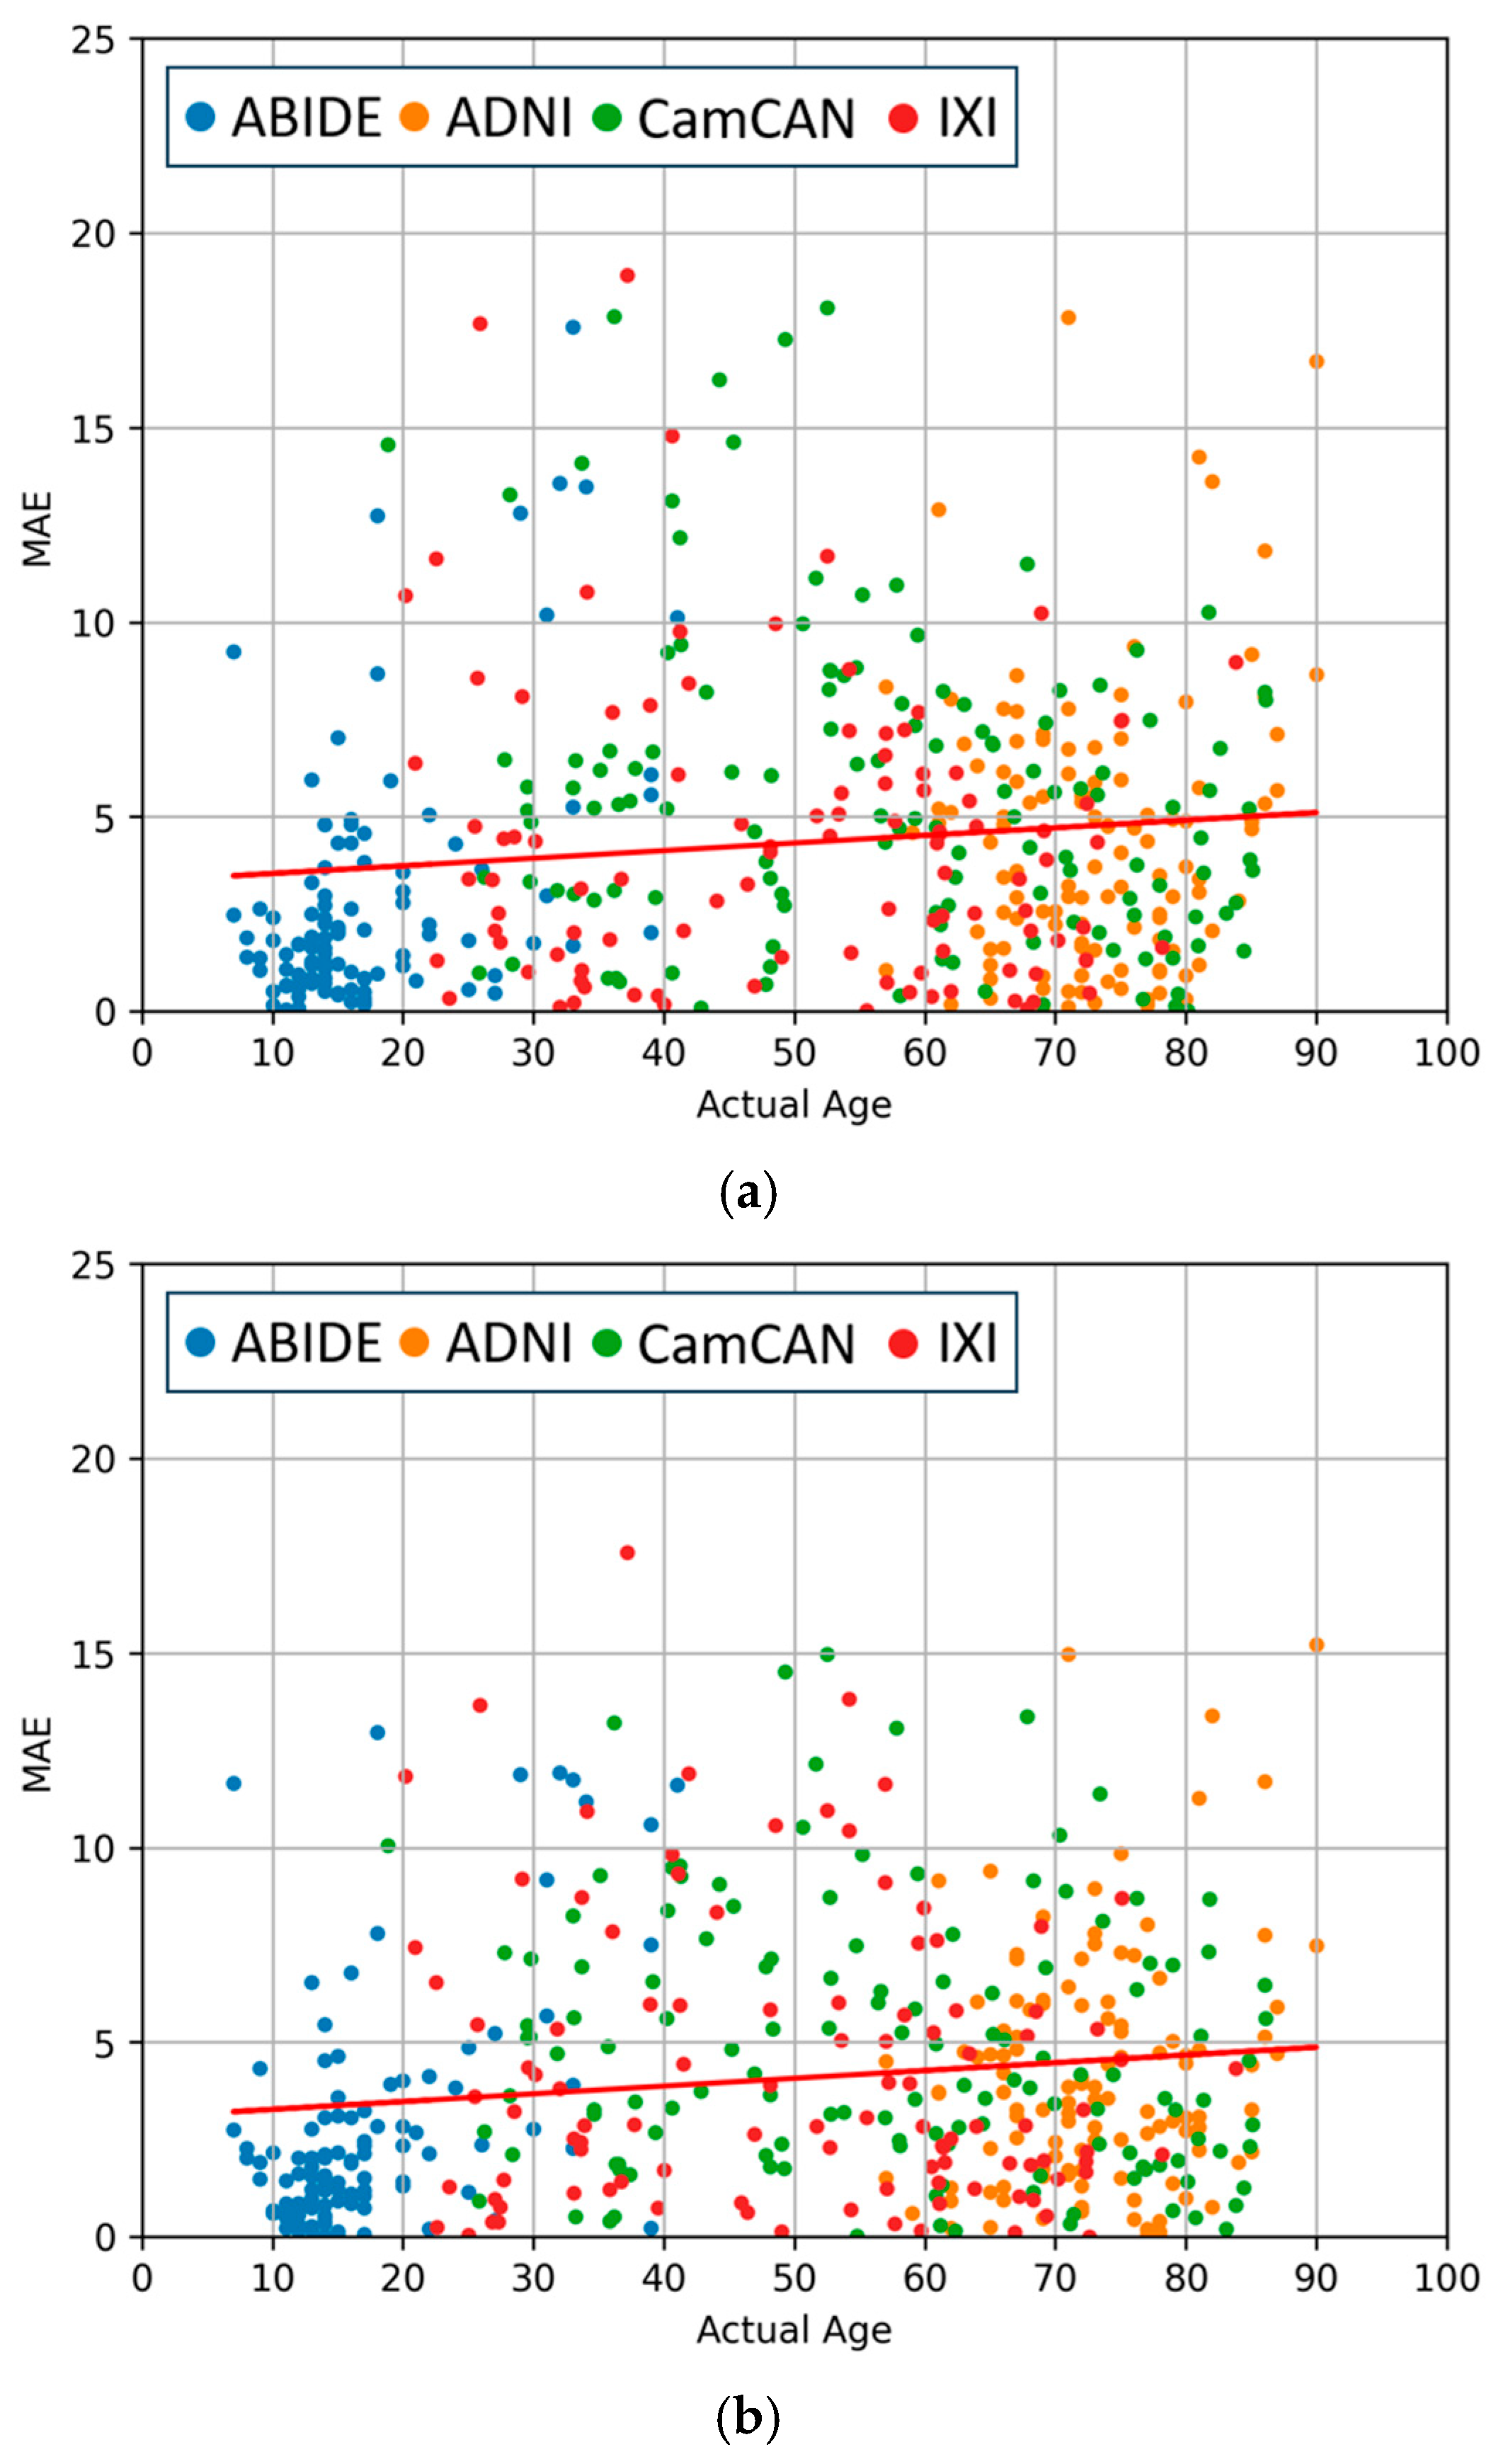

4.3. Comparisons of Regression and Softmax Performance

4.4. Evaluation of Data Augmentation